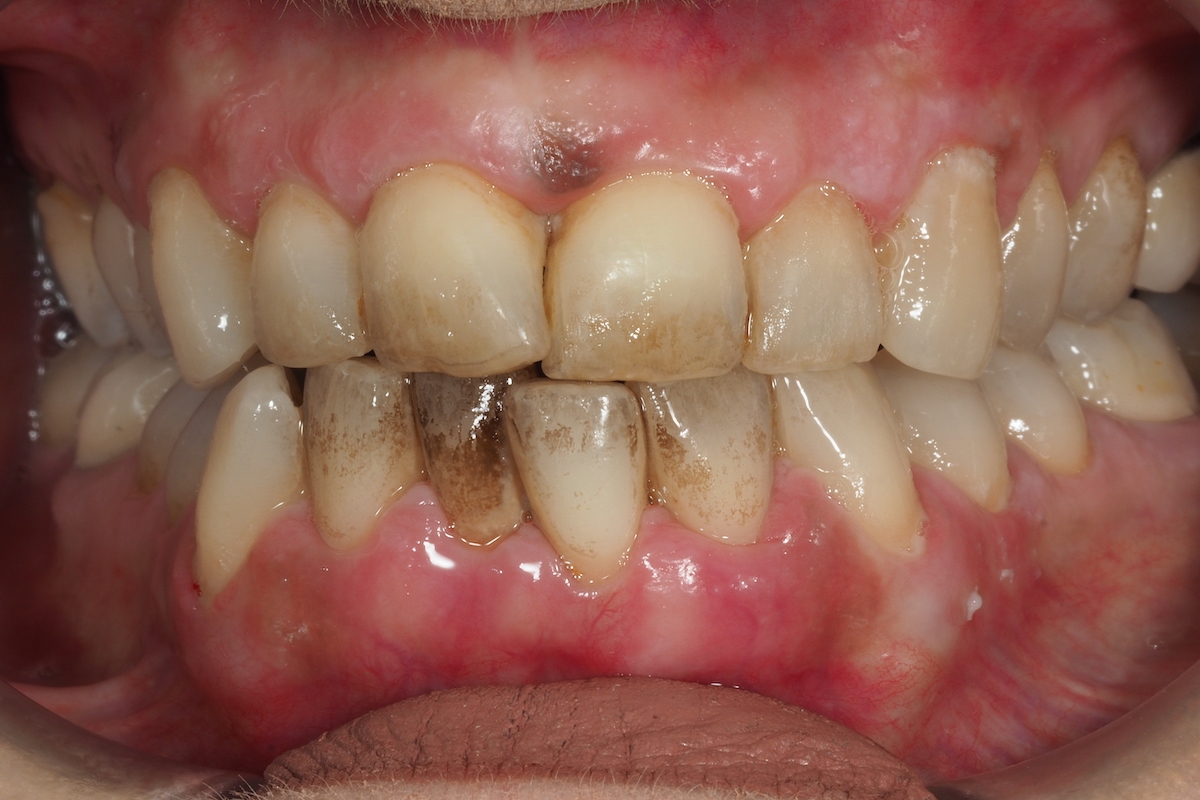

Caso de Periodoncia 4 | Periodontitis de fumador

Después Después

Antes Antes